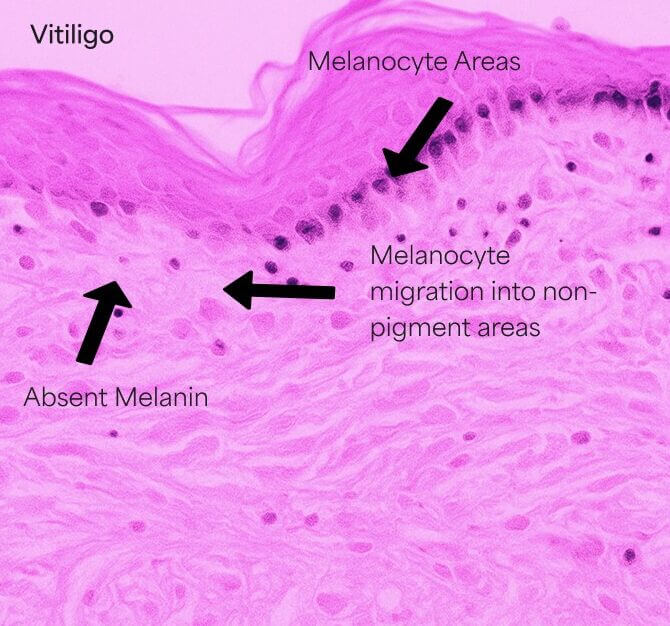

Hypopigmentierte Flecken

Hypopigmentierte Flecken entstehen, wenn pigmentproduzierende Zellen (Melanozyten) absterben oder die Melaninproduktion einstellen.

Die betroffenen Hautstellen werden heller oder weiß. Es ist unklar, was genau zum Ausfall oder Absterben dieser Pigmentzellen führt.

Es kann auf eine Autoimmunerkrankung, erbliche Faktoren oder auslösende Ereignisse wie Stress, Sonnenbrand oder chemisch bedingte Hautverletzungen zurückzuführen sein.

So funktioniert es

- Die Aktivierung, Migration und/oder Proliferation von Melanozyten in hypopigmentierte Bereiche an der dermoepidermalen Junktionszone (DEJ) soll induziert werden. Diese oberflächliche Dermis stellt die Zieltiefe dar.

- Darüber hinaus stimuliert ein mechanisches Trauma die Migration der Melanozyten von den pigmentierten Bereichen zu den unpigmentierten Bereichen.

- Durch Mikroneedling kann die Anzahl der Pigmentzellen erhöht und die Pigmentproduktion angeregt werden.

- Studien in der Fachliteratur deuten darauf hin, dass sechs oder mehr Behandlungen erforderlich sein können, um eine Besserung festzustellen.